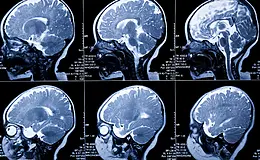

Edinilen bilgiye göre, 2 yaşındaki M.D.İ. adlı kız çocuğu evlerindeki salıncaktan düşerek yaralandı. Özel bir hastaneye kaldırılan M.D.İ. acil serviste tedavi altına alındı. Acil serviste görevli Dr. Ahmet Kurt, çocuğun çekilen tomografisini inceleyeceği sırada çocuğun babası H.İ. ile kardeşi Ş.İ.’nin saldırısına uğradı. Doktorun odasındaki bilgisayar yere düşüp zarar görürken, Dr. Kurt saldırıyı yara almadan atlattı. Hastaneye polis sevk edildi. Ağır yaralı olan çocuğun tomoğrafi filmini incelemek için başka odaya giden Dr. Ahmet Kurt, çocuğun beyin kanaması geçirdiğini tespit edince acil olarak Samsun Ondokuz Mayıs Üniversitesi Tıp Fakültesi Hastanesi’ne sevkine karar verdi. Çocuğu kırmızı odada sedyeye koyan Dr. Kurt, sevk sırasında ambulansta yanında olacak olan çocuğun annesine ne yapması gerektiğini anlattığı sırada çocuğun babası, Dr. Ahmet Kurt’a aniden yumruk atıp bununu kırıp yere düşürdü. Kanlar içinde kalan Dr. Ahmet Kurt, Samsun Eğitim ve Araştırma Hastanesi’ne kaldırılarak tedavi altına alındı. Hastaneye yatışı yapılan doktorun hayati tehlikesinin bulunduğu öğrenildi.Dr. Ahmet Kurt, “Düşme sonucu hastanemize gelen çocuğun filmini incelemek için sisteme düşmesini beklerken babası ve çocuğun amcası bana saldırdı. Kendimi korudum ancak bilgisayar kırıldı, masa dağıldı. Hastaneye polis gelince çocuğun filmini incelemek için başka odaya geçtim. Burada filmi inceleyip beyin kanamasını tespit edip Samsun Ondokuz Mayıs Üniversitesi Tıp Fakültesi Hastanesi’ne sevkine karar verdik. Çocuğun annesine ambulansta ne yapması gerektiğini anlatırken, çocuğun babası yumrukla bana saldırdı” dedi.Olayla ilgili H.İ. ile kardeşi Ş.İ. polis tarafından gözaltına alındı. Olayla ilgili soruşturma devam ediyor.